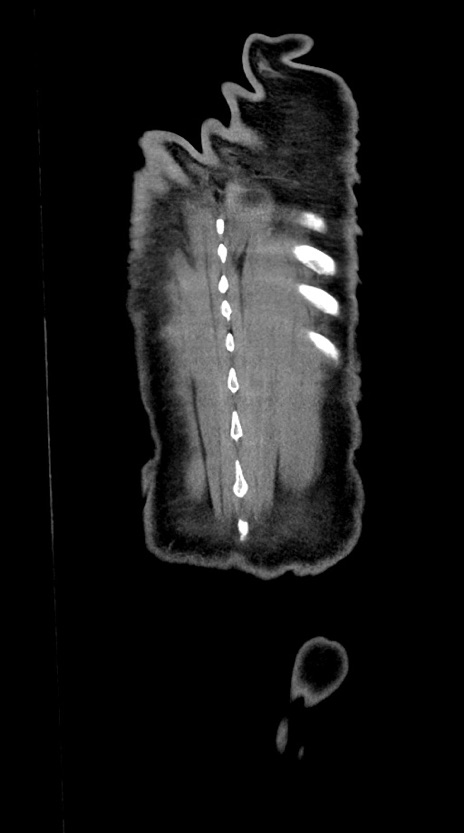

症例28(冠状断像)